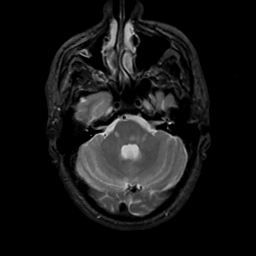

MR Study #7, March 24, 1991 -- Slice #12